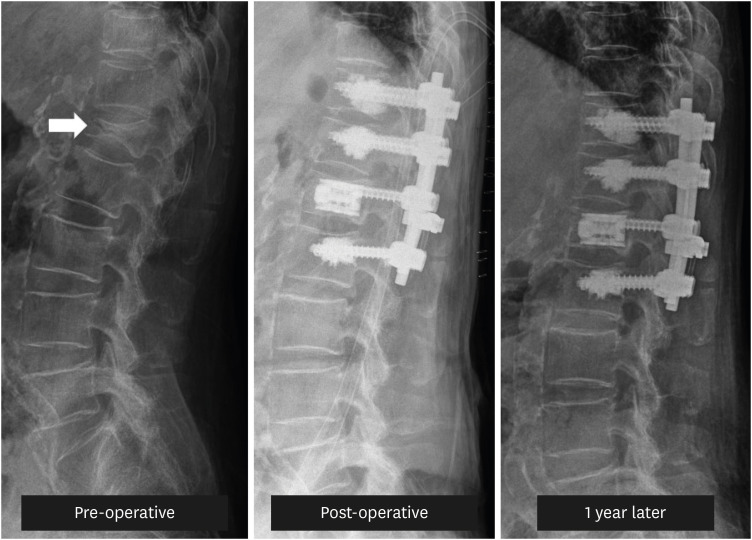

骨质疏松性椎体压缩骨折(OVCF)是导致老龄人口发病率和死亡率上升的重要原因。经年龄调整后,韩国是全球 OVCF 患病率最高的国家,男性每 10 万人中有 544 人,女性每 10 万人中有 1,575 人。此外,OVCF 患者发生其他骨折的风险更高,发生新的椎体骨折的风险最高可达 5 倍。因此,在治疗 OVCF 患者时,必须解决目前的症状,并采取预防措施防止进一步骨折。虽然药物治疗非常重要,但可能并不能满足所有 OVCF 患者的需求,更严重的患者通常需要物理治疗或手术干预。本综述旨在探讨针对 OVCF 患者的有效物理治疗方法,并总结针对患有各种基础疾病的高风险老年患者的手术技术。

Osteoporotic vertebral compression fractures (OVCF) significantly contribute to increased morbidity and mortality in aging populations. When adjusted for age, South Korea has the highest global prevalence of OVCF, with rates of 544 per 100,000 men and 1,575 per 100,000 women. Moreover, patients with OVCF are at a heightened risk of additional fractures, with the risk of new vertebral fractures being up to 5-fold higher. Therefore, in treating patients with OVCF, it is essential to address the current symptoms and take preventive measures against further fractures. Although pharmacological treatment is crucial, it may be insufficient for all patients with OVCF, with more severe cases often requiring physical therapy or surgical intervention. This review aimed to explore effective physical therapy methods for patients with OVCF and summarize surgical techniques for high-risk older patients with various underlying conditions.